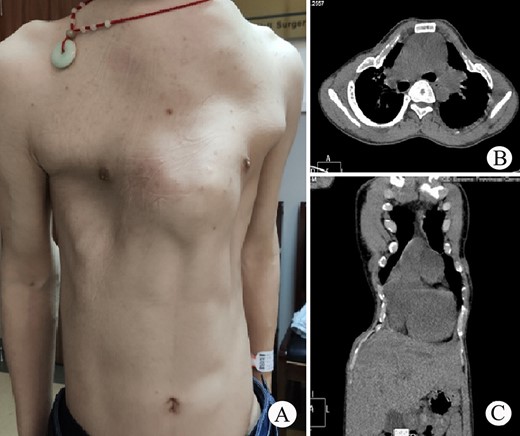

The patient was a 25-year-old man who had respiratory discomfort after birth and was diagnosed as ATD at that time. His respiratory symptoms were obvious in childhood. Hypoxia always appeared when crying but disappeared after rest. After age of 5, his condition gradually stabilized. However, after puberty, his respiratory symptoms reappeared and worsened 1 year before admission. He was admitted to our hospital for surgery finally. Physical examination showed that his thorax was narrow and small (Fig. 1A), and his height was 145 cm and chest circumference was only 63 cm. Imaging examination revealed that there were obvious depressions on both sides of the chest wall (Fig. 1B and C). The operation was carried out under general anesthesia, and performed on both sides of chest wall simultaneously. Two longitudinal incisions were performed on each sides of the chest wall respectively in the axillary midline to expose the ribs and costal cartilages. Two tunnels were made in front of the sternum but beneath the soft tissues of the anterior chest wall, and two arc-shaped steel bars were put into the tunnels, respectively. Both sides of the bars were located in front of the depressions. The structures in the depressions were lifted and fixed on the bars (Fig. 2A–C), and the depressions disappeared completely. After the incisions were closed, the operation was completed (Fig. 1D). The symptoms improved significantly, the blood oxygen saturation maintained over 92%, the chest circumference increased to 70 cm and the appearance of the chest was basically normal postoperatively. The patient was discharged 25 days after operation. Followed up for 1 year, there were no symptoms during daily activities, but there were hypoxia after vigorous activities. Imaging examination showed that the shape of the thorax was significantly improved (Fig. 3A and B).

(A) Thorax appearance before operation; and (B) and (C) CT scan of thorax.